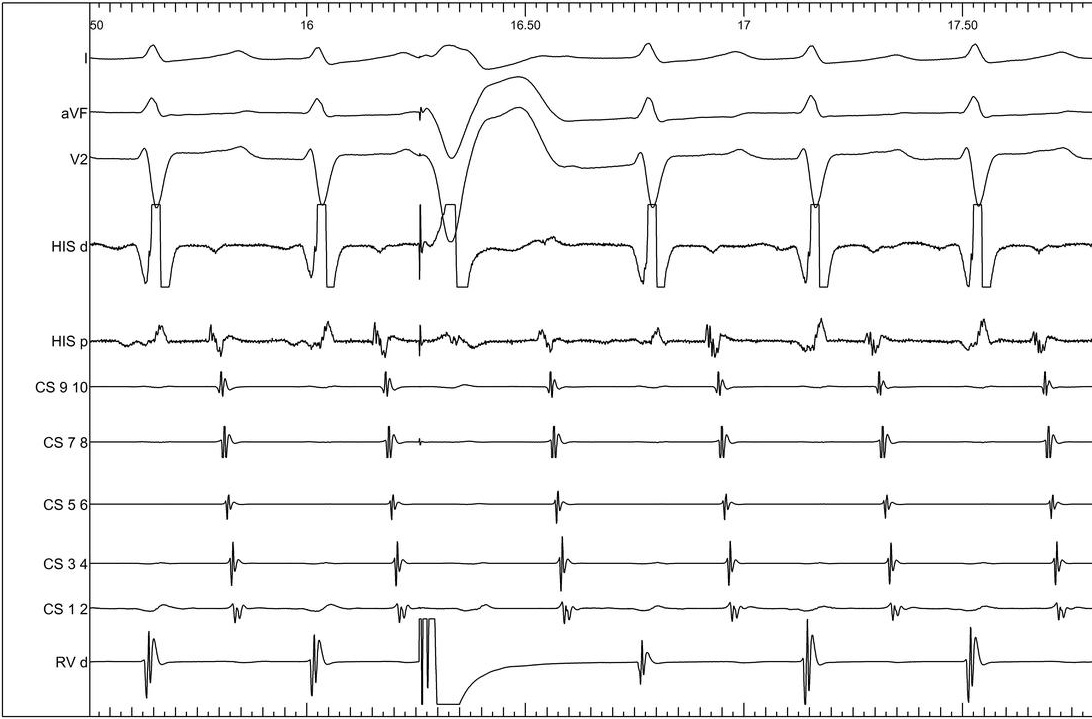

Burst atrial pacing

09_va_unlinking.jpg